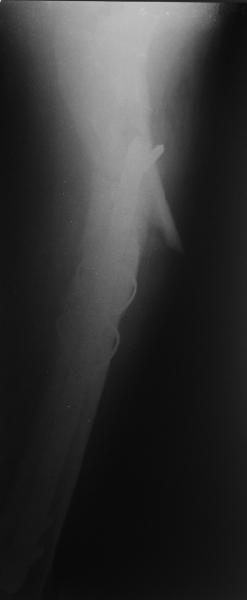

Изначально была выбрана не правильная точка введения стержня, в связи с чем в конце, я подчеркну, в конце операции произошло из-за напряжения между прокимальным концом канала бедра и стержнем разрушение в/3 бедра.

В общем, сделали. См. приложение.

Длина и из-за этого ось получились не совсем такие, как хотелось бы, все-таки срок после той операции уже 6 недель. Может быть, стоило провести дистракцию аппаратом неделю-другую. Заранее спасибо за комментарии и критику.

Очевидно была неправильно, причем, очень неправильно! точка введения штифта.